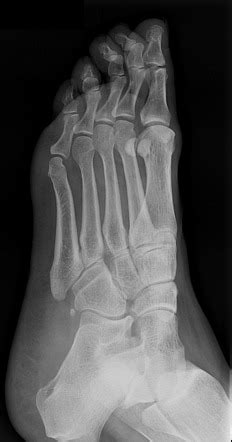

Painful os peroneum, fracture, diastasis. Fractures of the os peroneum present as pain localized on the lateral aspect of the foot resulting from direct trauma, muscle contraction, inversion injuries or chronic overuse injuries. Sx often mild, patients usually present with sprained ankle complaint.

X ray shows irregular, fragmented and possibly spread out appearance of osperoneum with soft tissue swelling in.

Fracture of the os peroneus with retraction of the peroneus longus tendon can lead to weakness, instability, and progressive foot deformity. Hiroyuki fujioka1, , takeshi kokubu2, takeshi makino2, issei nagura2, toshihisa maeda2, masahiro. Painful os peroneum, fracture, diastasis. Surgical excision and repair of peroneus longus tendon or tenodesis to peroneus brevis. Os peroneum treatment, etiology, epidemiology, natural history, anatomy, symptoms, xrays small accessory bone proximal to the base of the 5th metatarsal within the substance of peroneus longus. Subcutaneous peroneus longus tendon rupture associated with os peroneum fracture. Most common fracture at base of 5th metatarsal. Os peroneum is an accessory bone (ossicle) located at the lateral side of the tarsal cuboid, proximal to the base of 5th metatarsal, commonly mistaken for a fracture. Proposed treatment strategies for fracture of the os peroneum include. Brigido mk, fessell dp, jacobson ja, et al. Fracture of the os peroneum is relatively rare, and a stress fracture of the os peroneum is even rarer. Avulsion fracture of the os peroneum with pull of the. Fractures of the os peroneum are rare. Cureus accessory ossicles of the foot and ankle. Fractures of the os peroneum present as pain localized on the lateral aspect of the foot resulting from direct trauma, muscle contraction, inversion injuries or chronic overuse injuries. 578 x 430 jpeg 28 ΠΊΠ±. Fractures of the os peroneum present as pain localized on the lateral aspect of the foot resulting from direct trauma, muscle contraction, inversion injuries or chronic overuse injuries.